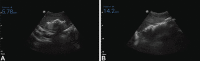

Experience: We successfully placed the mini-sponge device in nine patients experiencing postpartum hemorrhage after vaginal birth, with resolution of bleeding within 1 minute. The mean time to place the device was 62 seconds. Uterine fill was documented in all cases by ultrasound scan, and device placement was rated as "easy" to "very easy." Mini-sponges were left in place on average for 1 hour (0.5 hours-14 hours). Bleeding did not recur. There were no adverse events; all patients remained afebrile and did not require subsequent surgical intervention.